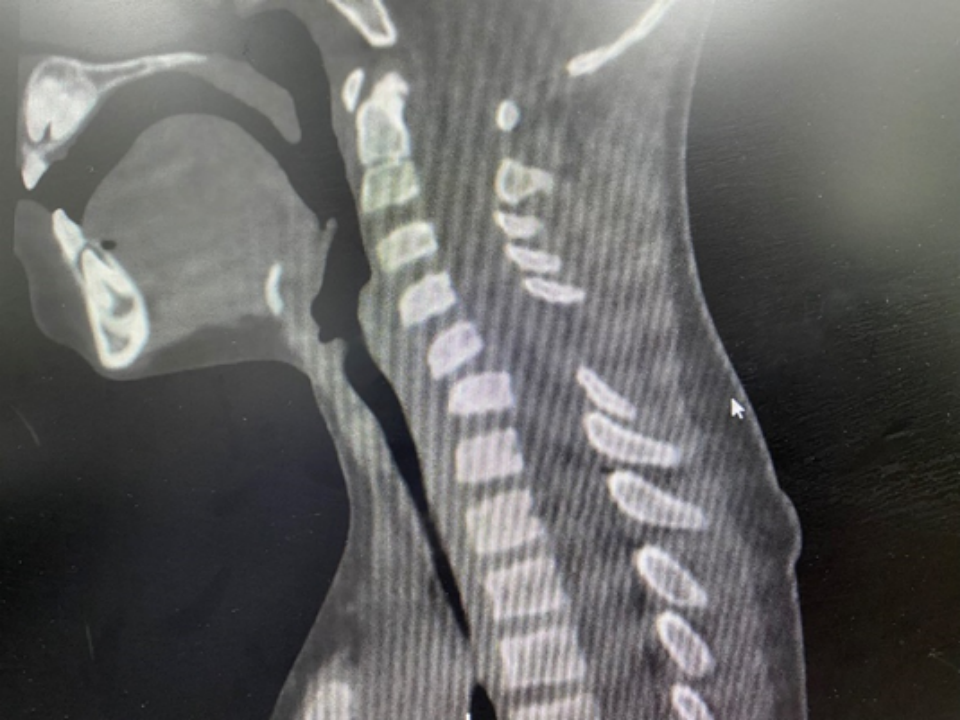

影像显示的颈椎 C5/C6 脱位,颈椎后凸以及颈部软组织损伤

图源:丁香园拍摄